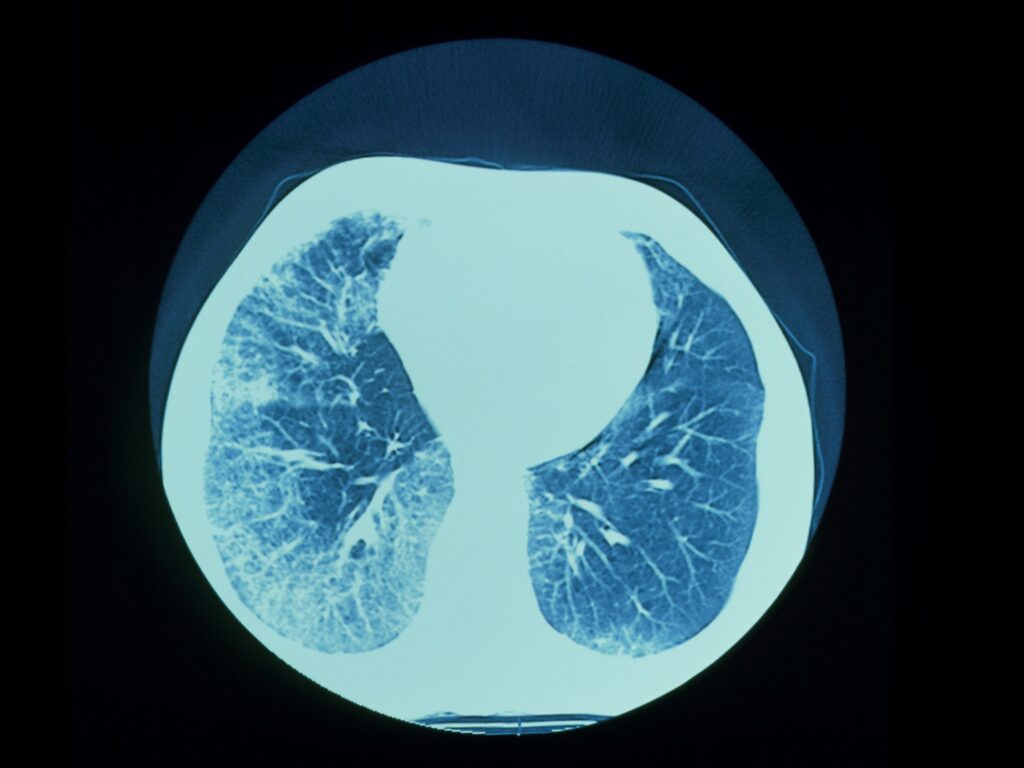

The Global Progressive Fibrosing Interstitial Lung Diseases Treatment Industry is poised for steady growth, according to market analysts. The market, valued at US$4,742.2 million in 2023, is projected to reach a significant US$8,654.1 million by 2033, reflecting a Compound Annual Growth Rate (CAGR) of 6.2%. This growth highlights the increasing focus on developing effective treatments for this complex and debilitating condition.

Technological advancements in healthcare stand at the forefront of this transformative journey, driving the market’s trajectory toward unprecedented heights. Factors such as the escalation in lung infection incidence heightened awareness among the populace, and robust governmental initiatives aimed at mitigating these infections serve as key catalysts propelling the growth of the global progressive fibrosing interstitial lung disease treatment market.